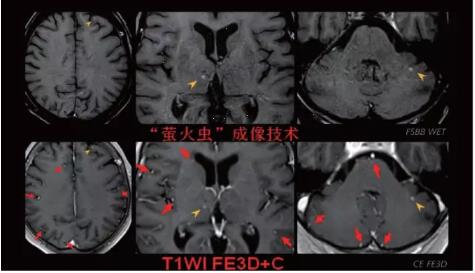

見(jiàn)所未見(jiàn) 微小腫瘤無(wú)處遁藏——

“螢火蟲(chóng)”成像技術(shù) 顱內腫瘤微小病灶檢出新發(fā)現

此技術(shù)主要用于神經(jīng)系統惡性腫瘤,以及其他腫瘤腦轉移瘤篩查。傳統情況下做腫瘤腦轉移篩查,很容易漏掉5mm以下小病灶,臨床發(fā)現后干預治療比較晚,要實(shí)現2mm高空間分辨率和超薄層全腦掃描在保證信噪比的情況下需要很長(cháng)時(shí)間大概十多分鐘,而且薄層增強序列顱內血管呈高亮信號,會(huì )干擾顱內小病灶的觀(guān)察,血管和小病灶區分困難。佳能”螢火蟲(chóng)”成像技術(shù)既可以實(shí)現高空間分辨率和超薄層(最薄可實(shí)現0.2mm)全腦掃描,掃描時(shí)間短,2-3分鐘即可實(shí)現全腦3D掃描,同時(shí)避免了血管高亮信號的干擾,對顱內原發(fā)或繼發(fā)的微小腫瘤檢查有重大意義。“螢火蟲(chóng)”成像技術(shù)具有磁敏感效應,對于亞急性血敏感敏感,可以區分出血和強化的腫瘤。